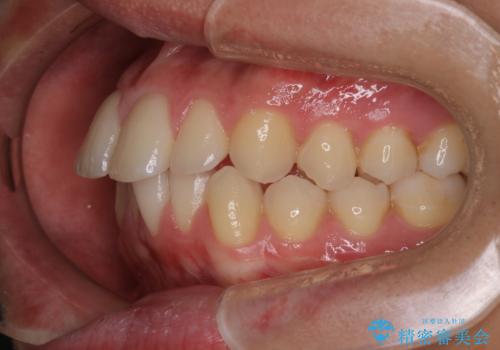

【インビザラインモニター】前歯が出ているのが気になる

- 上の前歯が出ているのが少し気になるとの事で来院されました。

インビザライン希望のため、IPR(歯と歯の間を削る処置)を行うことで、前歯の位置とがたつき整える治療計画を立てました。